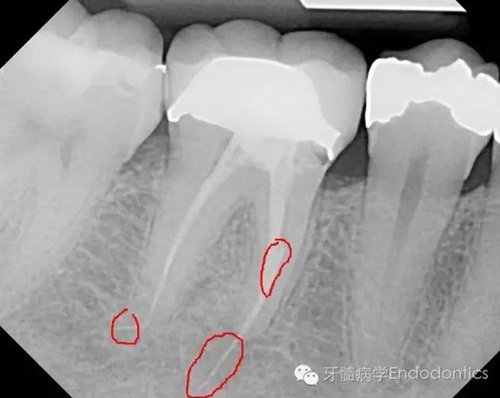

兩年后復(fù)診,病變愈合。

圖6.隨訪兩年后X線片